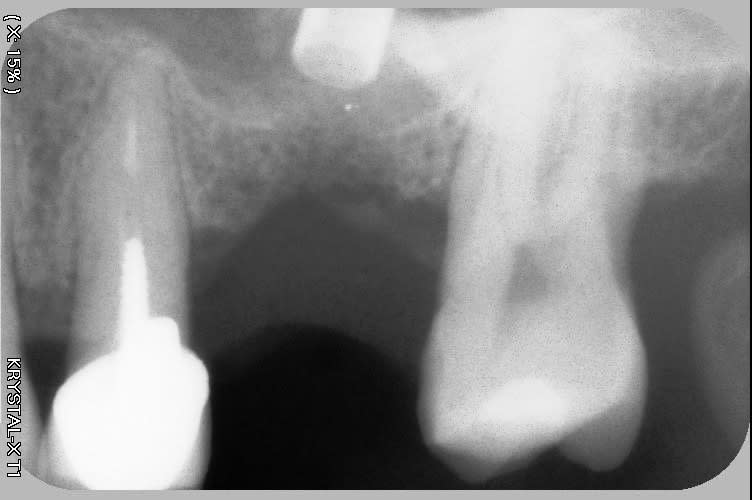

Bonjour, c'est une pano mais j'ai des doutes sur la position et l'enfouissement de certains implants.

"Oui la pano est assez trompeuse notamment sur le secteur 2 , j’ai décollé très légèrement la gencive en per opératoire pour toucher mon rebord cristal avec une sonde pari afin de vérifier l’enfouissement"

Lors de l'anesthésie j'ai remarqué une modification du volume gingival qui s'estompe mais pas complètement. Dans ce cas il me semble que le guide n'était pas en place, que l'analyse du volume osseux soit perfectible (certainement un cone beam) ... une pano reste un examen qui ne peu pas avoir un contrôle de la dimension volumétrique.

Je trouve que c’est assez flagrant que les implants sont trop vestibulaires….

Une grosse crête gingivale ne veut pas dire grosse crête osseuse